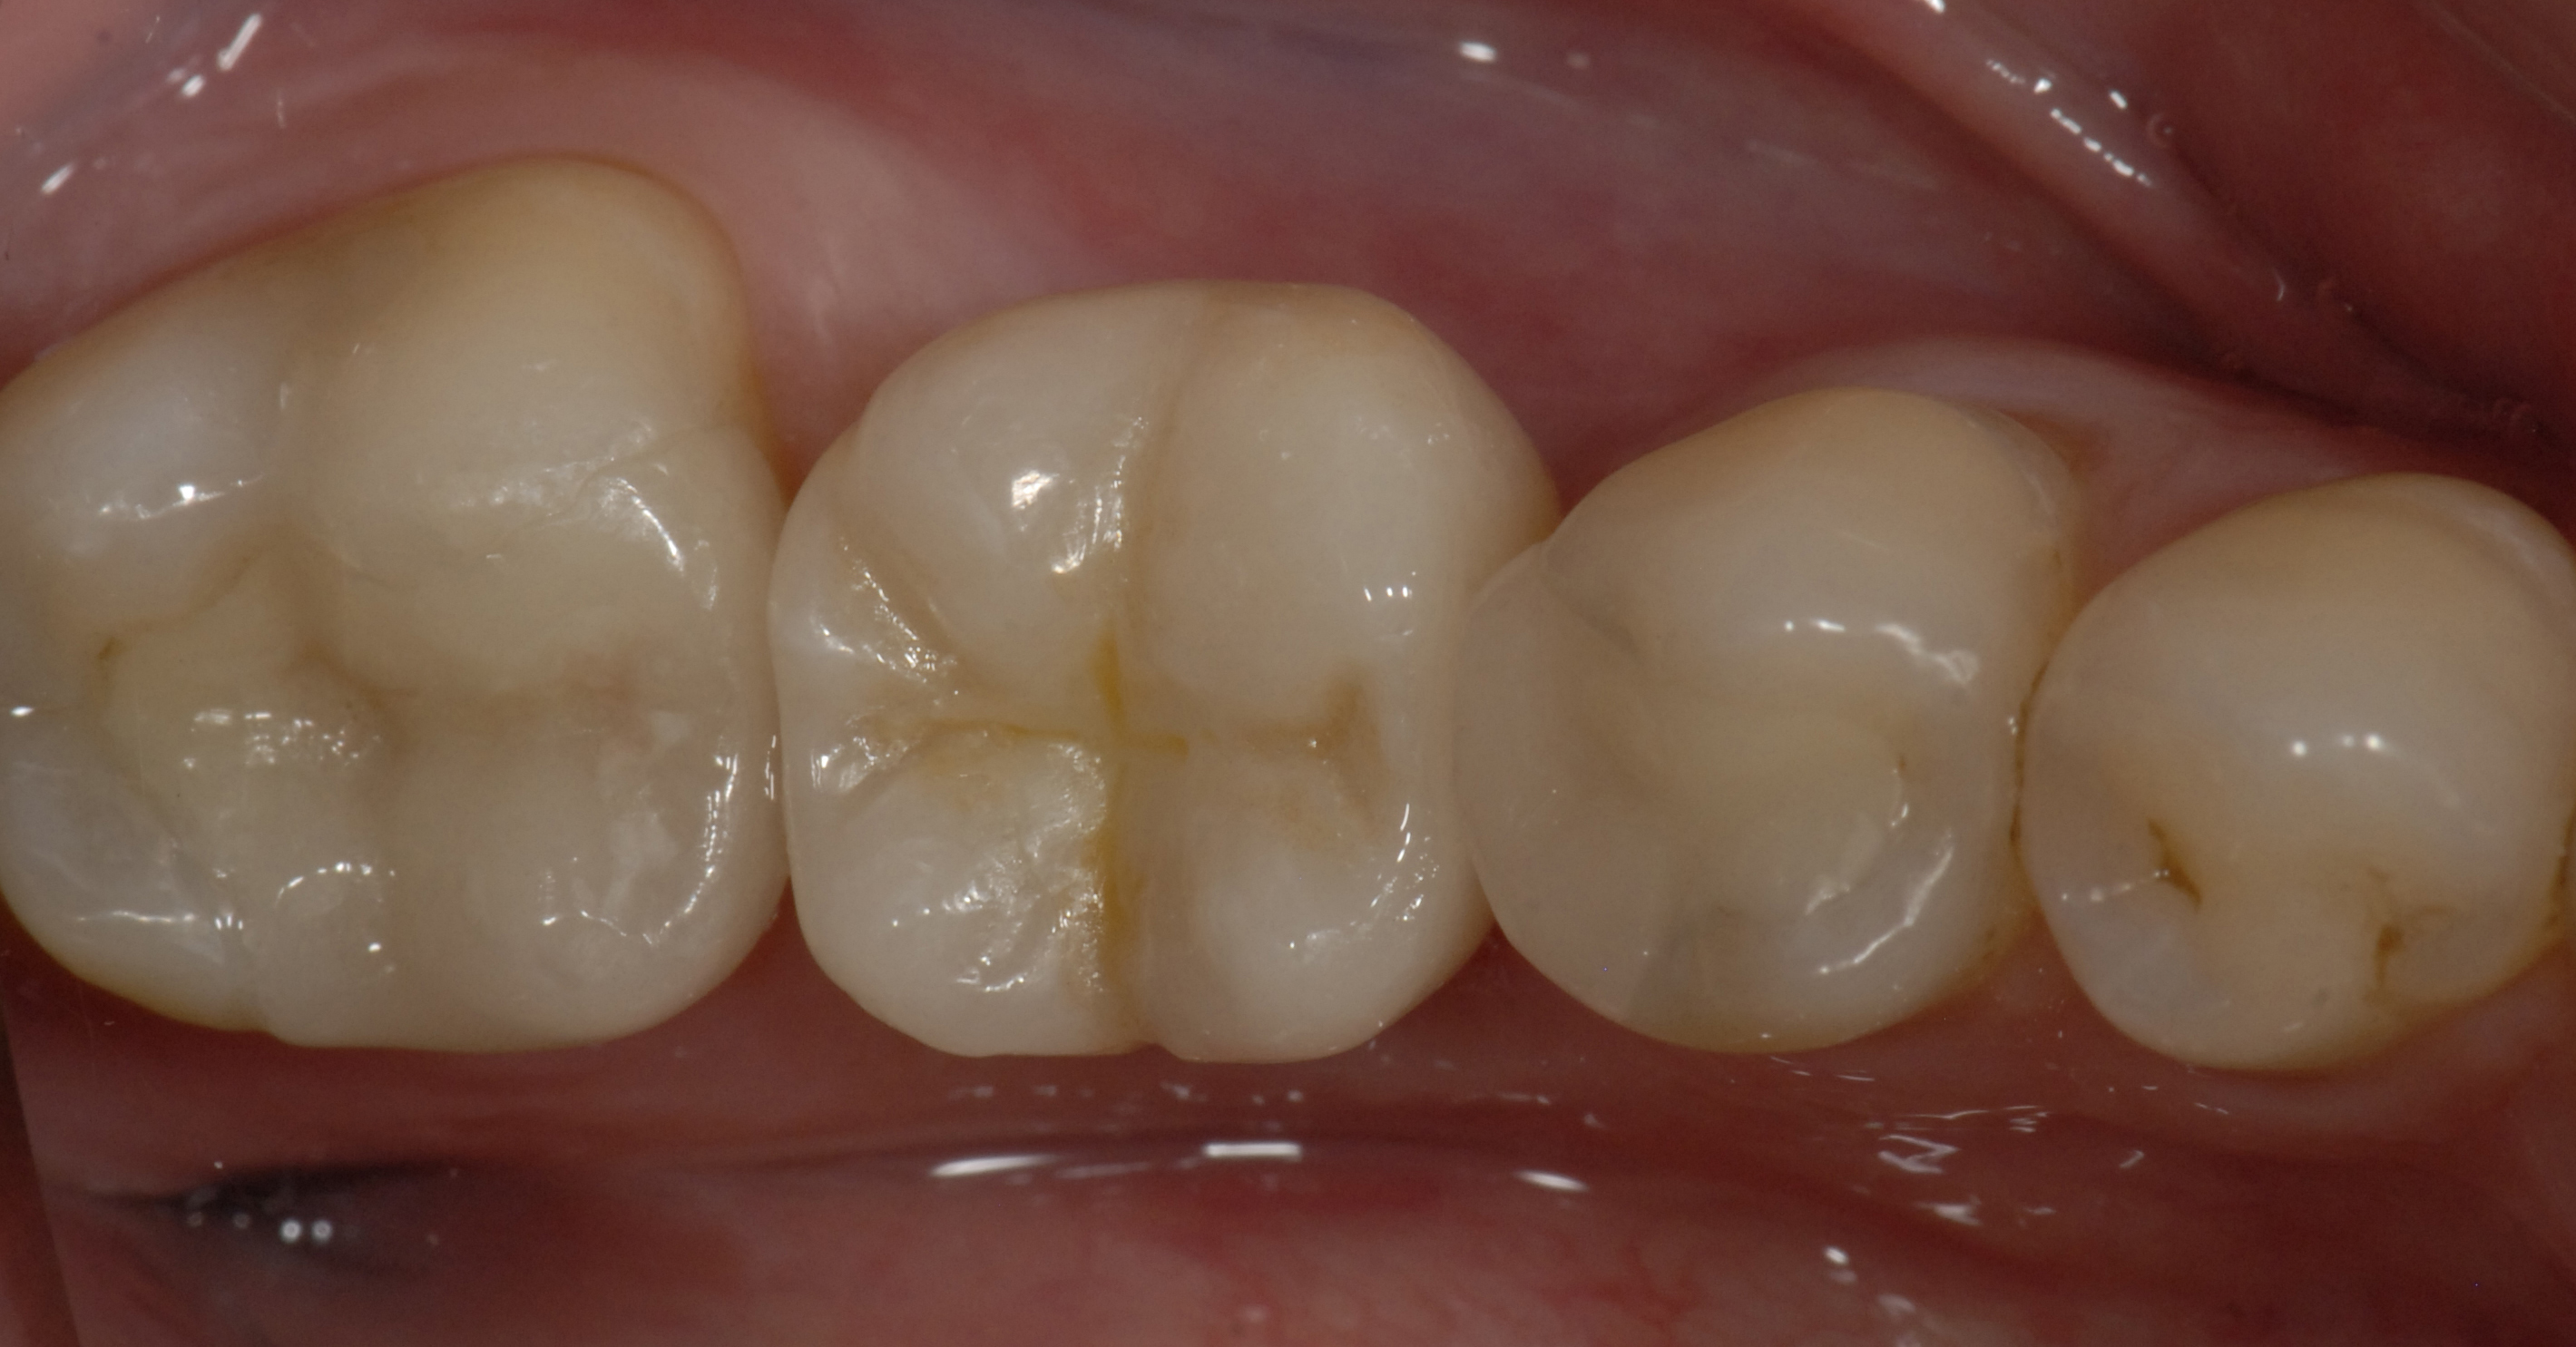

L’intégration esthétique des restaurations d’usage trans-vissées réalisées par CFAO est exceptionnelle. En effet ces restaurations monolithiques, par opposition aux restaurations céramo-métalliques pour lesquelles la céramique cosmétique doit être soutenue par l’infrastructure métallique, présentent une grande quantité de céramique surplombant le fût de vissage. Le comblement de ce fût par du téflon recouvert de composite permet de masquer totalement l’embase en titane et la vis de trans-fixation (Fig. 14 a, b et c).

Fig. 13 : Comblement du fût de vissage

13a : Mise en place de composite

13b : Maquillage des sillons

13c : Résultat final